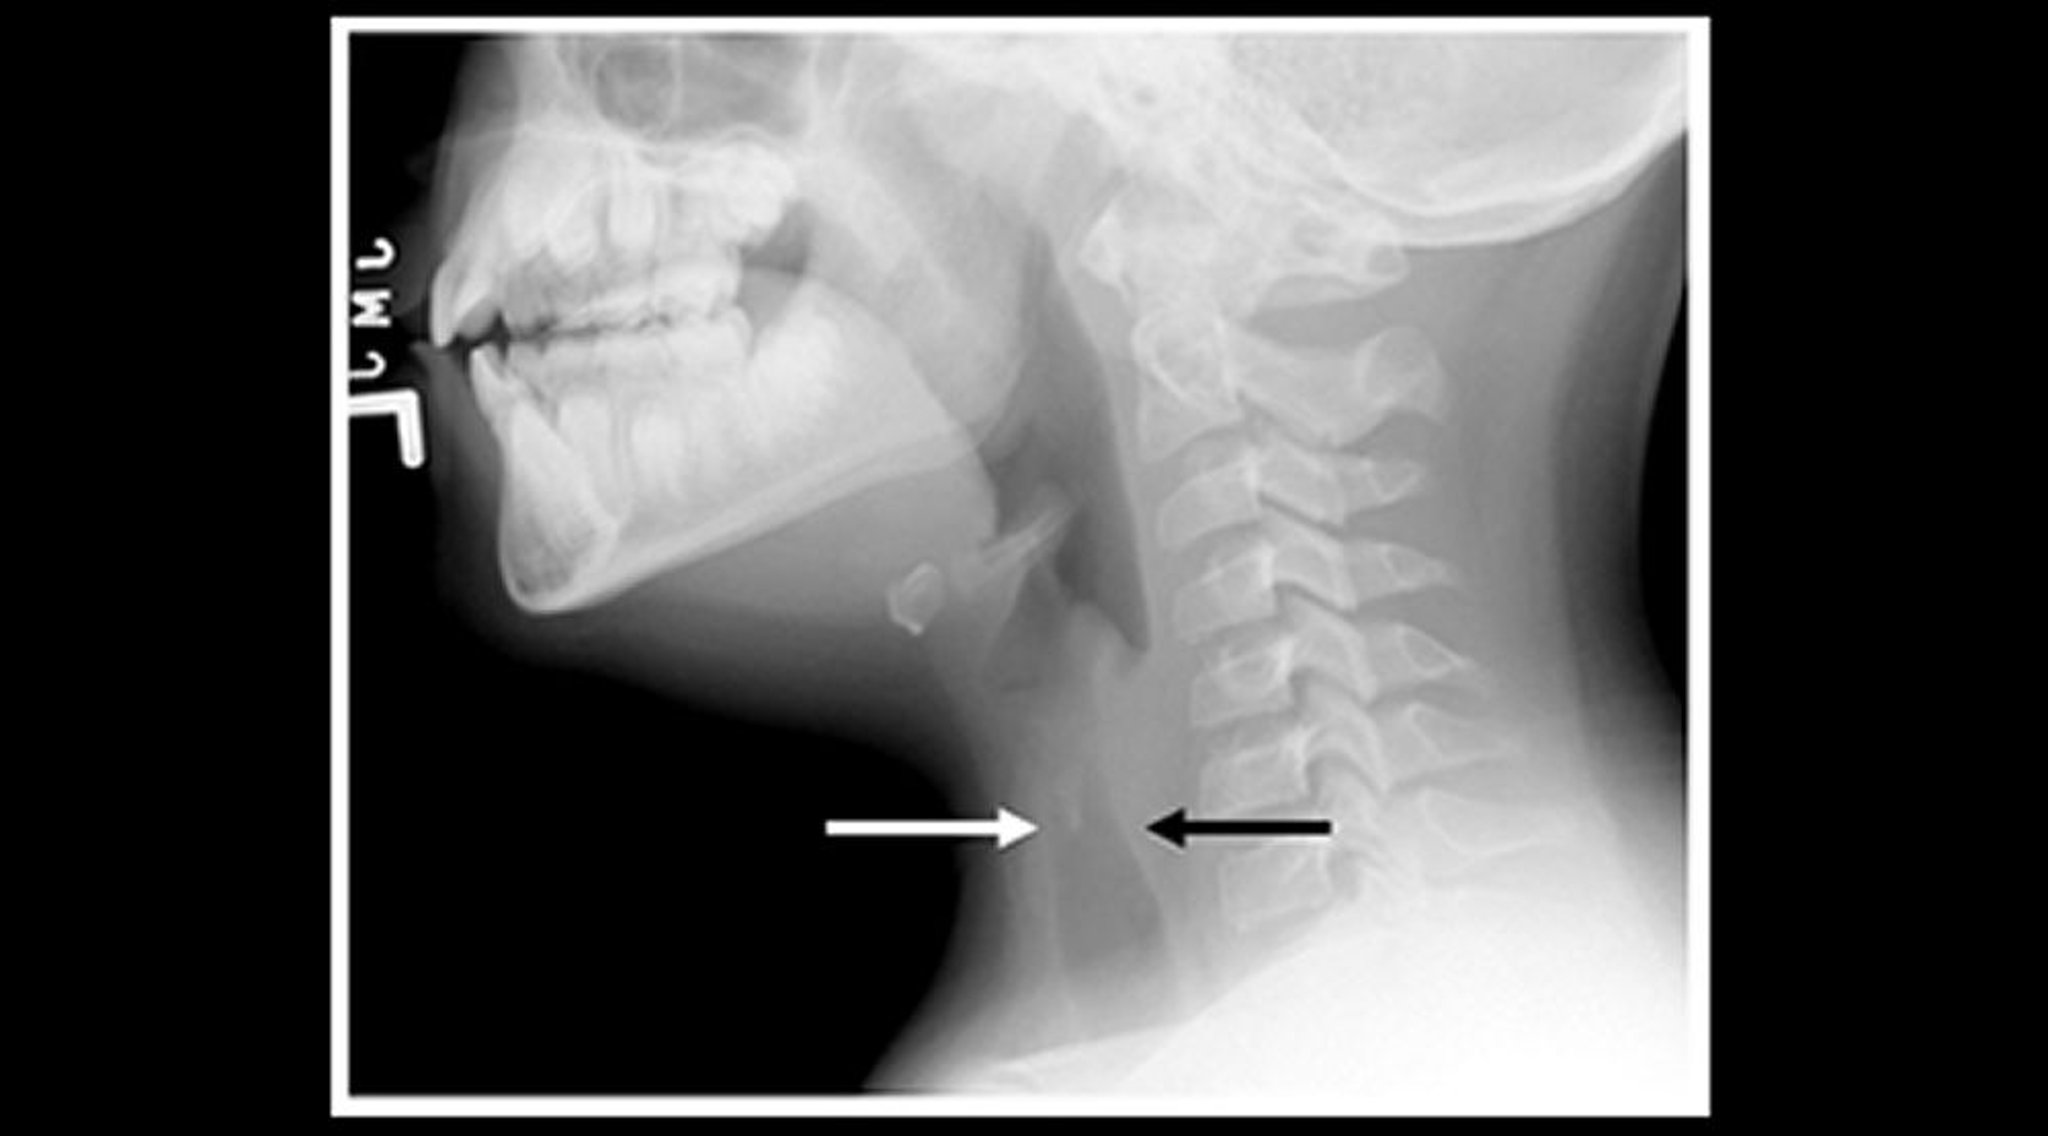

Если диагноз неясен, пациентам нужно провести передне-задний и боковой рентгены шеи и груди; субэпиглоттическое сужение (знак шпиля), выявляемое на передне-заднем рентгене шеи, подтверждает диагноз. Тяжелобольные пациенты с эпиглоттитом должны быть осмотрены в операционной соответствующим специалистом, способным установить поражение дыхательных путей (см. Лечение эпиглоттита). Пациентам необходимо проводить пульсоксиметрию, а тем, у кого имеется респираторный дистресс, можно измерять уровень газов в артериальной крови.

• Диагноз, как правило, ставится на основании клинических данных, но если в передне-задней проекции рентгенограммы шеи и грудной клетки видно классическое сужение подскладочного пространства гортани (симптом шпиля), то это подтверждает диагноз.